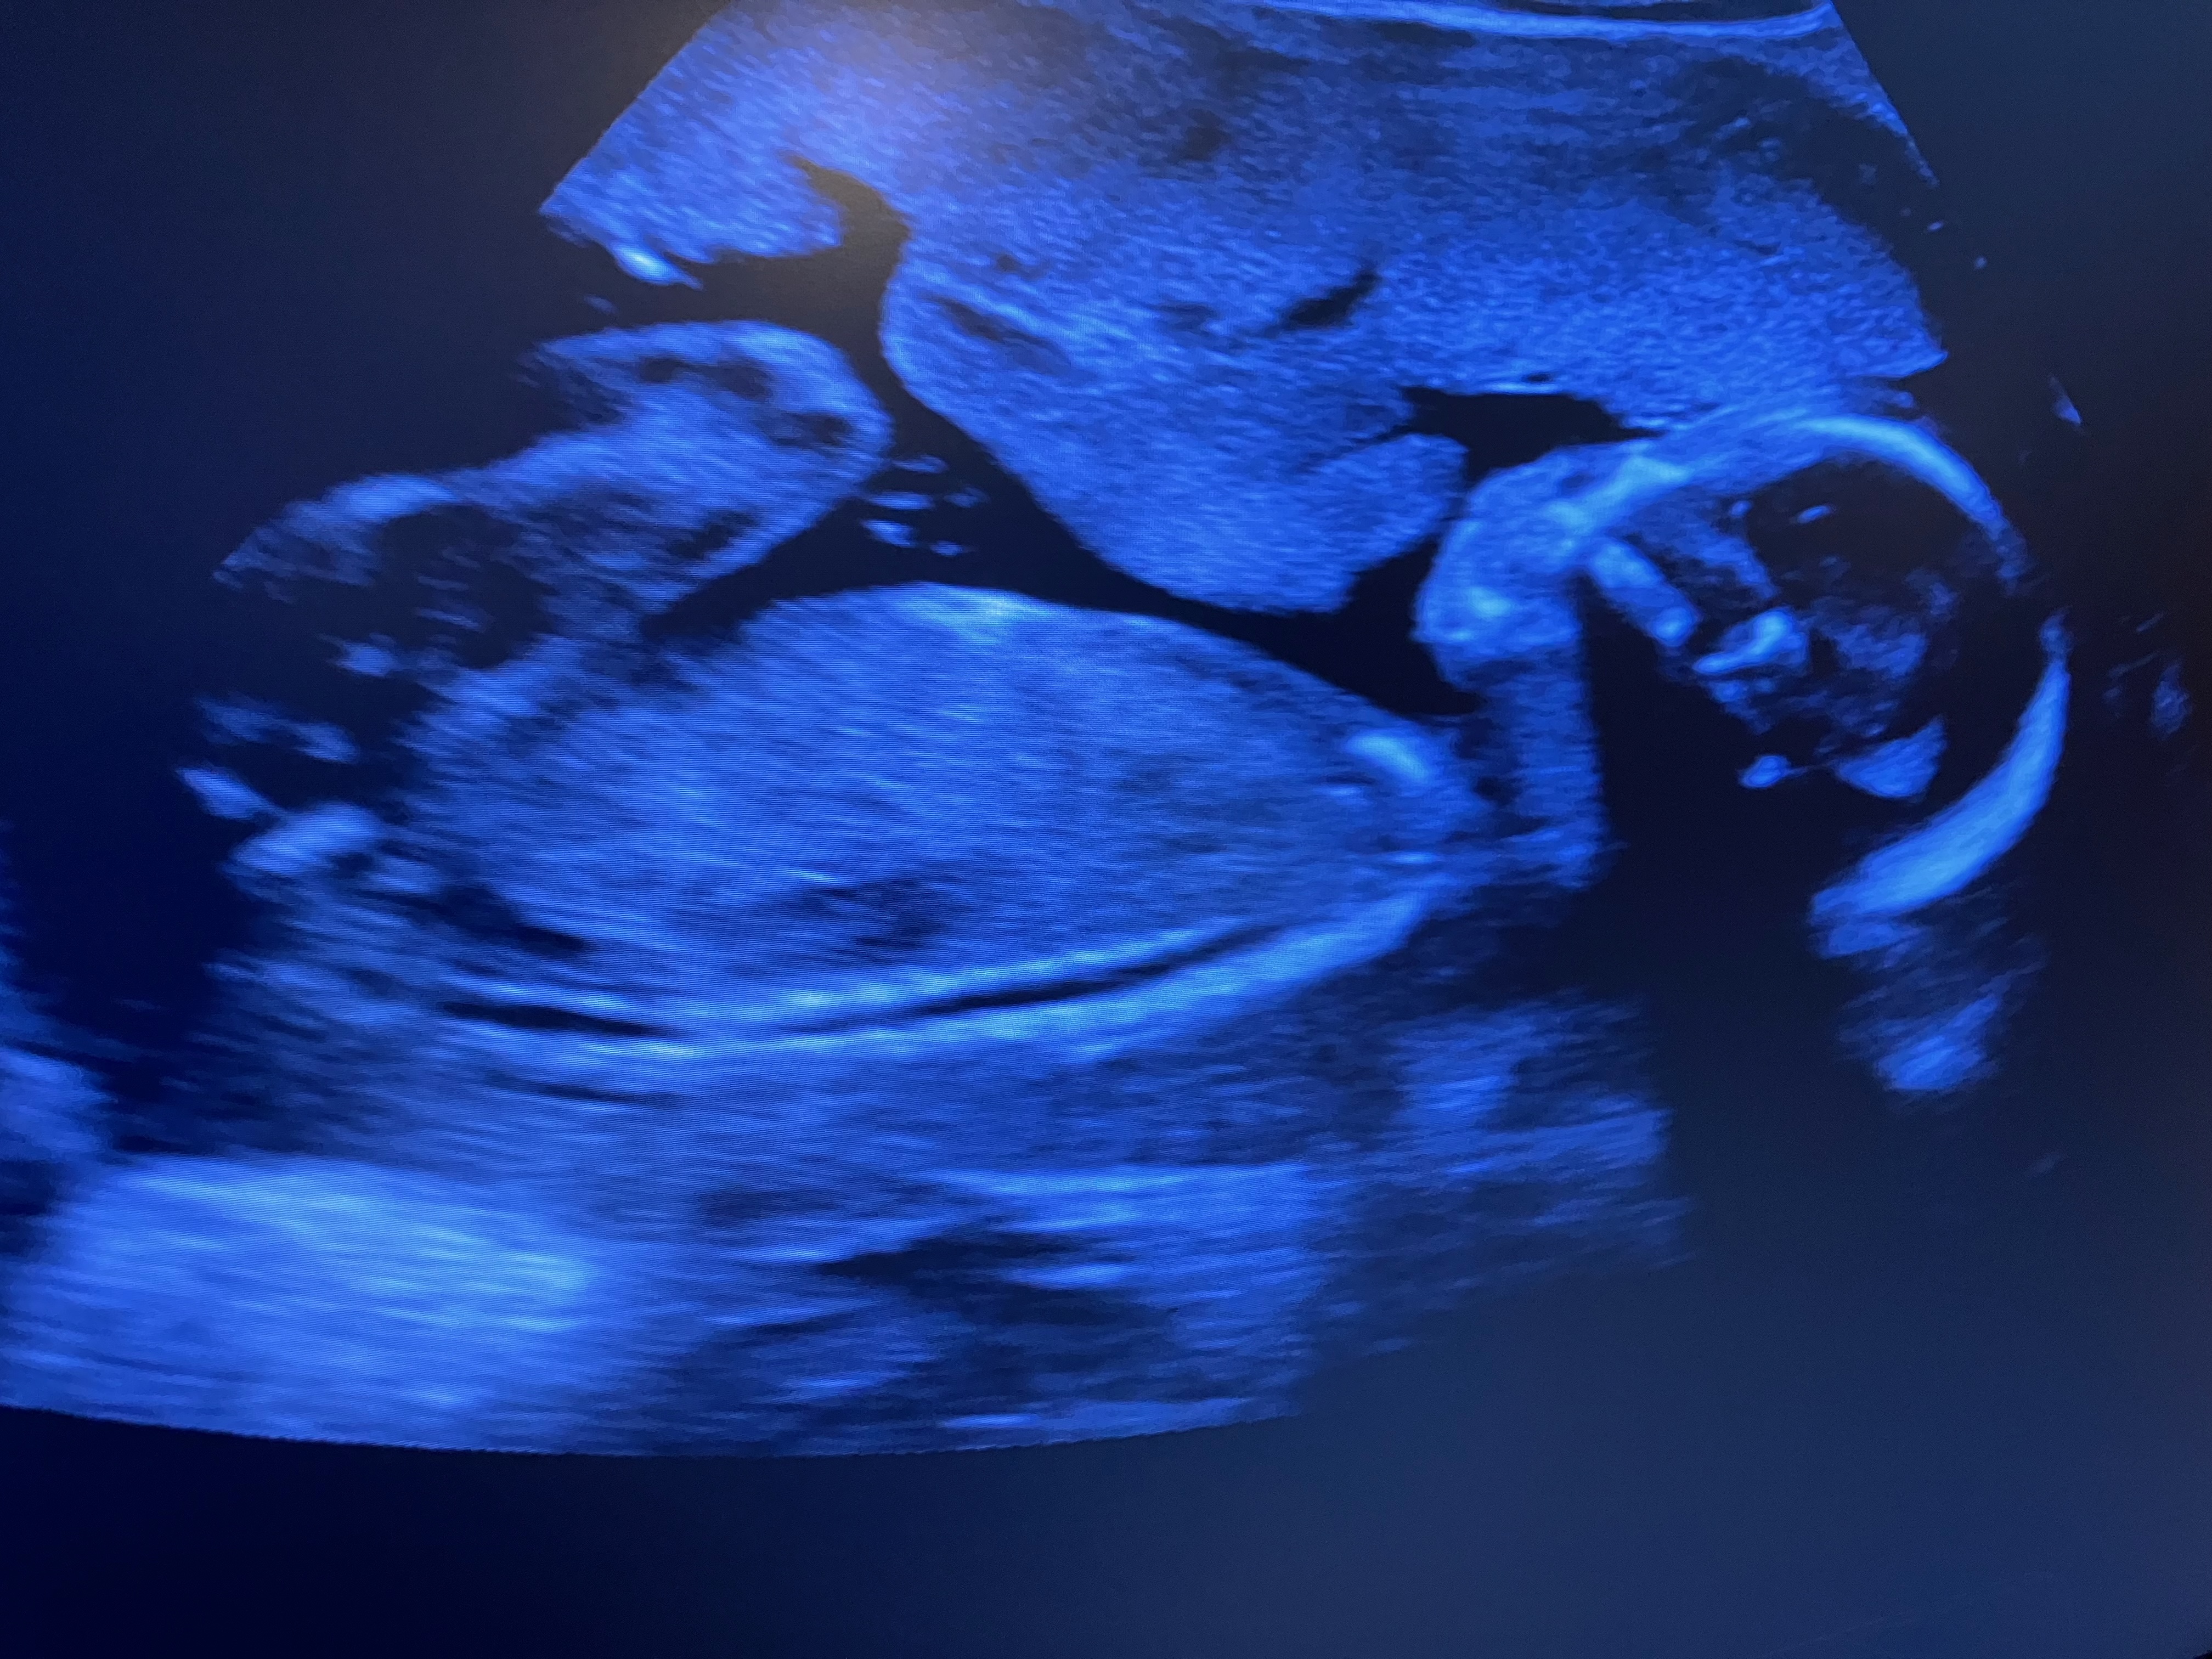

Happy Saturday everyone! I hope you are having a wonderful day so far. We have some exciting news that we found out Wednesday after school that I would like to share with everyone. But before I do, the doctor said Elizabeth is looking healthy and normal at this stage in her pregnancy, the doctor also said the little one is looking normal at this stage. Perhaps the baby is a little taller based on his estimated leg length. So Praise God for helping Elizabeth and the little one!

Now, time for the big reveal! We……………………………. are…………………………. having……………………… a……………………………………………………………………………………………………………………………………………………… ……………………………………………………………………………………………………………………………………………………………………………………………………baby………………………………………………………………………………………………………………………………………………………………………………………………………………………………………………………………………………………………………………………………………………………………………………………………………………………………………………………………………………………………………………………………………………………………………………………………………………………………………………..

boy!

Yes, the Howard family will have another baby boy! It was somewhat of a surprise, but we all are still happy! Thankfully we can start narrowing down the name list and I think we have decided on

Jonah Riley Howard for Howard Baby #3!